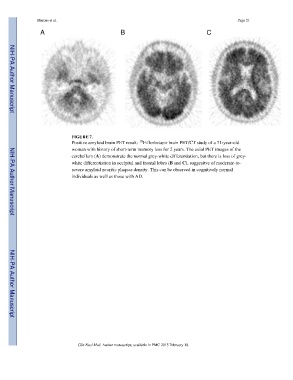

FIGURE 7.

Positive amyloid brain PET result: F-florbetapir brain PET/CT study of a 71-year-old

woman with history of short-term memory loss for 2 years. The axial PET images of the

cerebellum (A) demonstrate the normal grey-white differentiation, but there is loss of grey-

white differentiation in occipital and frontal lobes (B and C), suggesitve of moderate-to-

severe amyloid neuritic plaques density. This can be observed in cognitively normal

individuals as well as those with AD.